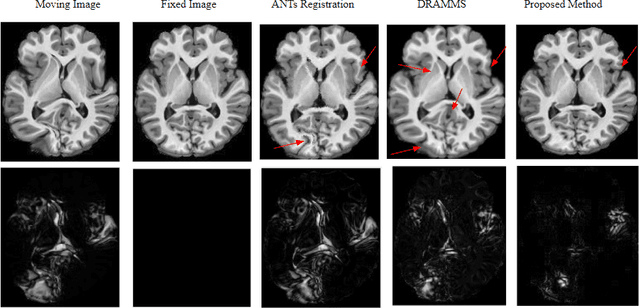

Anatomical variabilities seen in longitudinal data or inter-subject data is usually described by the underlying deformation, captured by non-rigid registration of these images. Stationary Velocity Field (SVF) based non-rigid registration algorithms are widely used for registration. SVF based methods form a metric-free framework which captures a finite dimensional submanifold of deformations embedded in the infinite dimensional smooth manifold of diffeomorphisms. However, these methods cover only a limited degree of deformations. In this paper, we address this limitation and define an approximate metric space for the manifold of diffeomorphisms $\mathcal{G}$. We propose a method to break down the large deformation into finite compositions of small deformations. This results in a broken geodesic path on $\mathcal{G}$ and its length now forms an approximate registration metric. We illustrate the method using a simple, intensity-based, log-demon implementation. Validation results of the proposed method show that it can capture large and complex deformations while producing qualitatively better results than the state-of-the-art methods. The results also demonstrate that the proposed registration metric is a good indicator of the degree of deformation.